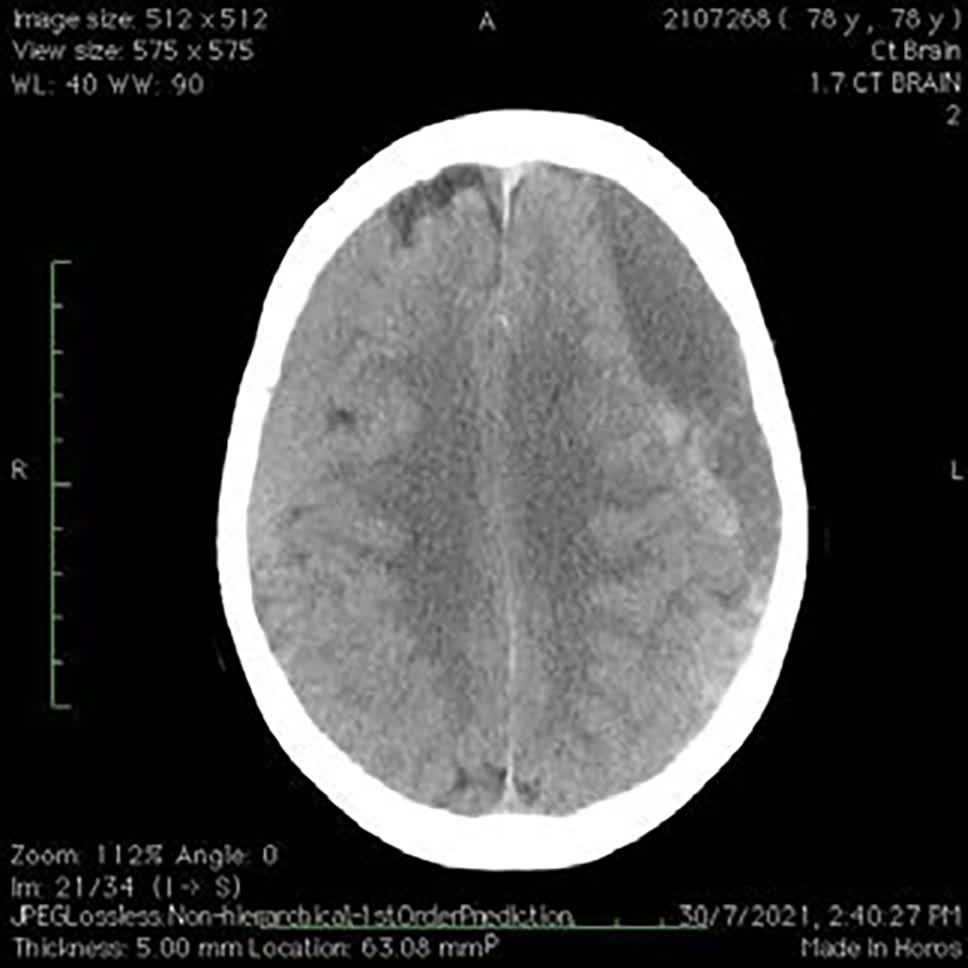

長者腦部日漸萎縮,與頭骨之間容易產生虛位。頭部創傷即使僅屬輕度或中度,腦內積聚的瘀血再少,亦會被身體吸收而化為血水,有機會在意外後約一至六個月內不斷膨脹,最終導致慢性硬膜下出血。患者反應會變得遲緩,步履不穩,嚴重者甚至會出現偏癱,建議立即求醫,接受腦掃描檢查。

傷者求醫時,醫生會先觀察相關臨床症狀,如言語不清等。如有需要,病人可接受電腦掃描或磁力共振,了解傷者顱骨受損程度,以及是否出現腦出血等。